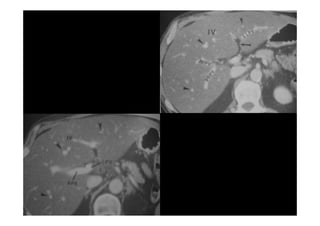

ANATOMIA SEGMENTAR DOFÍGADO ANATOMIA SEGMENTAR DO FÍGADO (COUINAUD) (COUINAUD) • • LOBO CAUDADO SEG. I LOBO CAUDADO SEG. I • • SEGMENTO SUPERIOR LATERAL ESQUERDO SEG.II SEGMENTO SUPERIOR LATERAL ESQUERDO SEG.II • • SEGMENTO INFERIOR LATERAL ESQUERDO SEG III SEGMENTO INFERIOR LATERAL ESQUERDO SEG III • • • • SEGMENTO MEDIAL ESQUERDO SEG IV SEGMENTO MEDIAL ESQUERDO SEG IV • • SEGMENTO INFERIOR ANTERIOR DIREITO SEG V SEGMENTO INFERIOR ANTERIOR DIREITO SEG V • • SEGMENTO SUPERIOR ANTERIOR DIREITO SEG VII SEGMENTO SUPERIOR ANTERIOR DIREITO SEG VII • • SEGMENTO INFERIOR POSTERIOR DIREITO SEG VI SEGMENTO INFERIOR POSTERIOR DIREITO SEG VI • • SEGMENTO SUPERIOR POSTERIOR DIREITO SEG VIII SEGMENTO SUPERIOR POSTERIOR DIREITO SEG VIII

ANATOMIA SEGMENTAR DO FÍGADO

(COUINAUD)

• LOBO CAUDADO SEG. I

• SEGMENTO SUPERIOR LATERAL ESQUERDO SEG.II

• SEGMENTO INFERIOR LATERAL ESQUERDO SEG III

• SEGMENTO MEDIAL ESQUERDO SEG IV

• SEGMENTO INFERIOR ANTERIOR DIREITO SEG V

• SEGMENTO SUPERIOR ANTERIOR DIREITO SEG VII

• SEGMENTO INFERIOR POSTERIOR DIREITO SEG VI

• SEGMENTO SUPERIOR POSTERIOR DIREITO SEG VIII